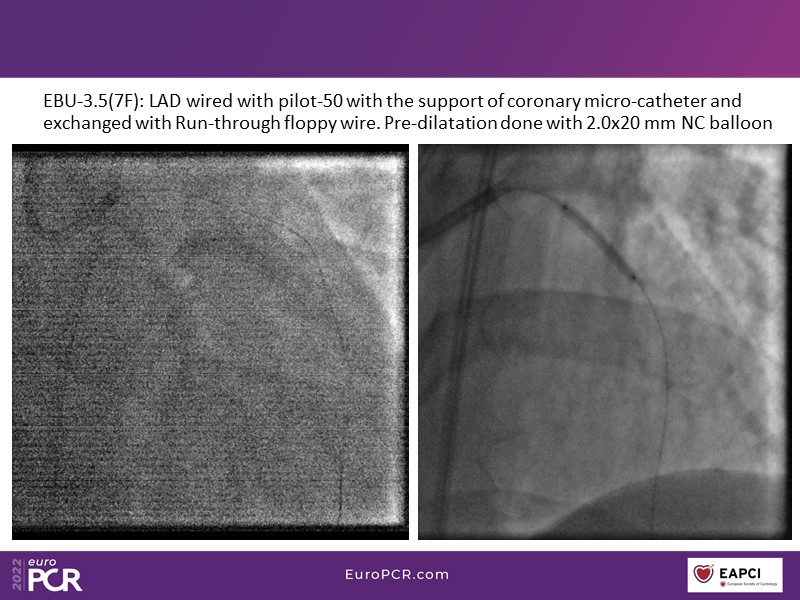

- To find out more about the application and mechanism of a sirolimus coated balloon for coronary artery disease treatment with case presentations in complex settings